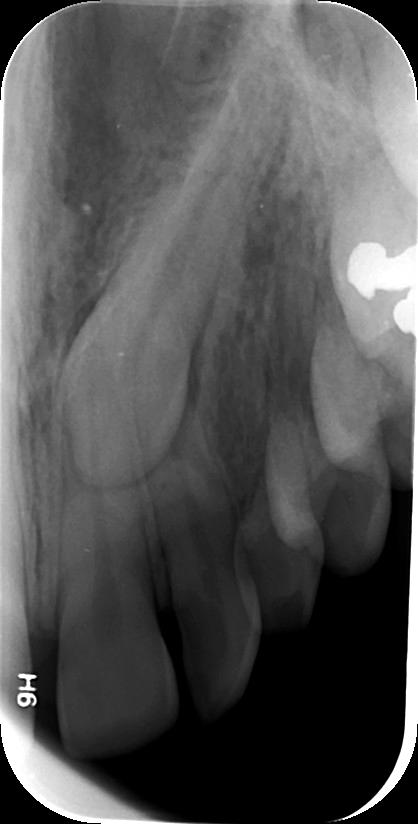

4. ΑΚΤΙΝΟΓΡΑΦΙΑ ΔΗΞΕΩΣ

Πρόκειται για ενδοστοματική ακτινογραφία κατά την οποία το πλακίδιο-φιλμ τοποθετείται οριζόντιο στο επίπεδο των δοντιών του ασθενούς (μασητικό επίπεδο) και συγκρατείται στη θέση του με το κλείσιμο του στόματος. Η πηγή ακτινοβολίας τοποθετείται κάθετα στο πλακίδιο, είτε άνωθεν του ασθενούς εάν θέλουμε να απεικονίσουμε την άνω γνάθο και υπερώα (ουρανίσκο), είτε κάτωθεν του ασθενούς εάν θέλουμε να απεικονίσουμε την κάτω γνάθο και το έδαφος του στόματος.

Με την εξέταση αυτή μπορούν να απεικονιστούν:

• το έδαφος του στόματος για την ύπαρξη λίθων στον εκφορητικό πόρο των σιελογόνων αδένων (Υπογνάθιος και Υπογλώσσιος)

• η εντόπιση, κλίση και φορά έγκλεισης (παρειο-γλωσσική ή παρειο-υπερώϊα) έγκλειστων και υπεράριθμων δοντιών, καθώς και η θέση τους σε σχέση με άλλα δόντια

• η παρειογλωσσική/παρειοϋπερώϊα ανάπτυξη παθολογικών αλλοιώσεων των γνάθων

• κατάγματα των γνάθων και των δοντιών

• υπερωο-γναθοσχιστίες.

Η λήψη της είναι γρήγορη (διαρκεί λίγα δευτερόλεπτα) και ανώδυνη.